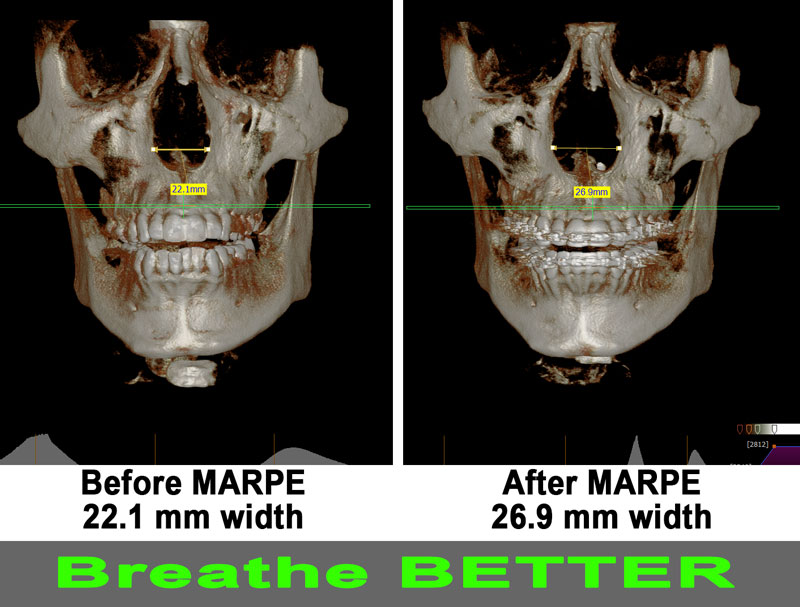

Does MARPE really help to increase the size of my nasal airway?

Research has shown that MARPE – IF DONE CORRECTLY - can successfully expand the nose up to 80% of the actual expansion of the MARPE expansion.

Here's the case Dr. Kanaan treated in his office with a patient who gained significant expansion in her nose, and she got rid of her mouth breathing.

This patient has been on allergy medications for years to improve their breathing. However, after watching Dr. Kanaan with Debra Duncan talking about MARPE and its benefits, he decided to undergo the MARPE procedure. Dr. Kanaan placed the MARPE with longer screws to maximize its force. His case was a complete success with over 5 mm of expansion in his basal nose level. Patient was pleased with his MARPE treatment in Houston.

Notice the excellent expansion on the X-ray and how it was filled with bone.